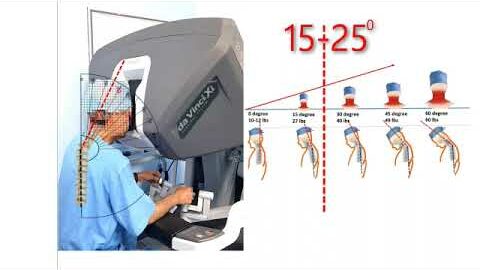

Our Experiments With (da Vinci) Xi

Urology, Wellbeing ';